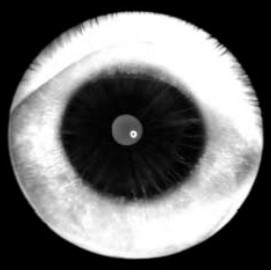

- По мере развития заболевания в пигментном листке появляются и прогрессируют сквозные дефекты, приводя в тяжелых случаях к аниридии с визуализацией неизмененных цинновых связок.

Исходно имеет место недоразвитие стромы и аномальная гипертрофия пигментного листка (в 34,5 раза выше нормы), что ведет к снижению прочности и эластичности радужки. Было выявлено, что постепенно происходят механическое растяжение и разрывы радужки, уменьшается ее площадь, но резко увеличивается толщина. Это сопровождается эктопией зрачка, затем появляются тонкие радиальные дефекты периферии пигментного листка, которые постепенно увеличиваются до огромных сквозных треугольных отверстий основанием к лимбу.

У больных нередко имеются аномалии зрачка: дистопия, неправильная форма, гипертрофия или отсутствие пигментной каймы. Схожесть внешних изменений радужек, их последовательность и типичность создают впечатление близкого родства совершенно несвязанных между собой пациентов.

Глазное дно: отмечается расширенная физиологическая экскавация диска зрительного нерва (ДЗН), стремящаяся к переходу в краевую; в центральной области существенных изменений не выявлено.

Глазное дно: ДЗН с едва заметной физиологической экскавацией; центральная область без патологии.